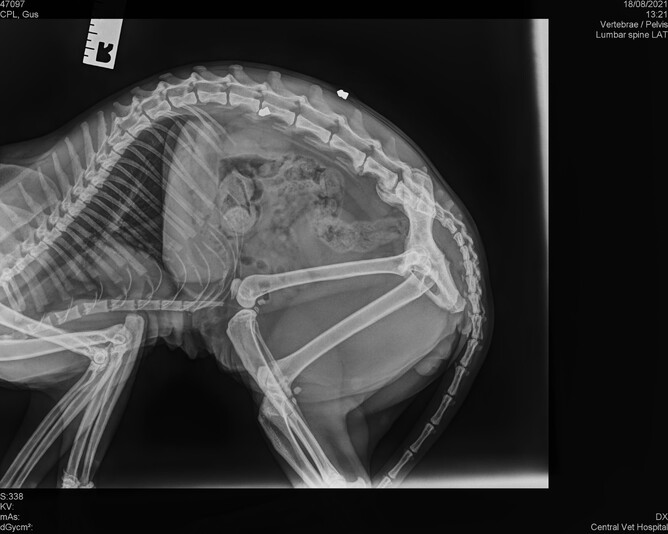

He is still cautious of new people, doesn’t like being picked up, and a long pat down his back shows the location of one of two shotgun pellets still buried in his back.

An x-ray also revealed the buried pellets (pictured below), but it was decided to leave them where they were as they didn’t appear to be causing Gus any discomfort.